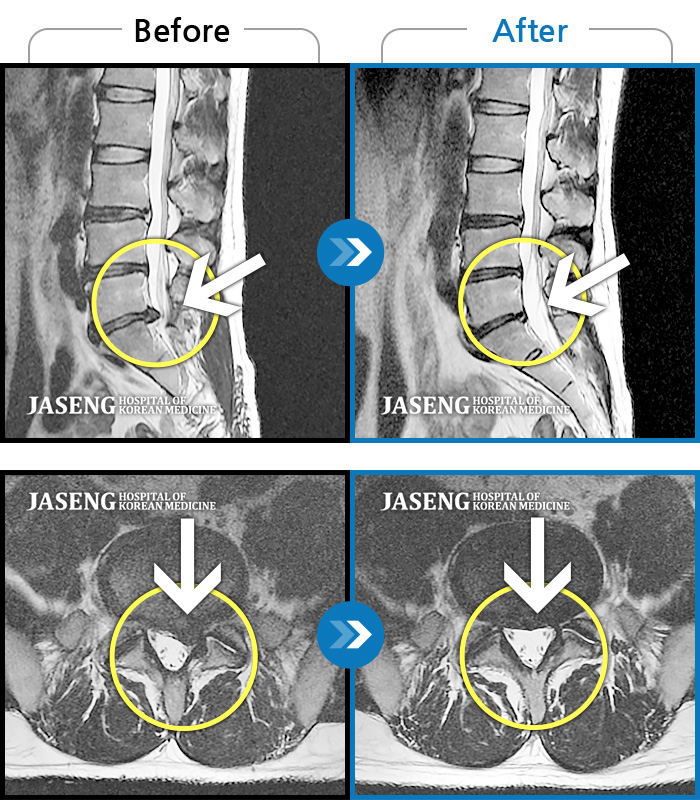

MRI 치료사례

오른쪽 다리가 저리고 아프며 골반이 좌측으로 편위된 상태였습니다.